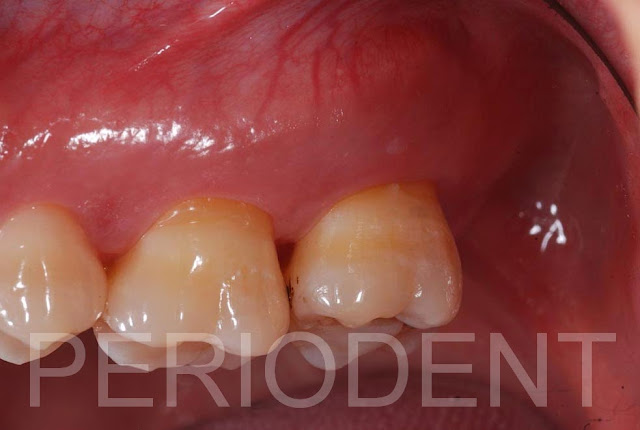

患者左上第二大臼齒顎側常常牙齦腫脹,經牙周探針測量有10mm深的囊袋

牙周手術翻開翻瓣後,見到Palatal Root有嚴重的牙結石堆積,及齒槽骨破壞

清除牙結石及發炎組織後,發現根尖懸浮在骨缺損內,且可見到鼻竇膜